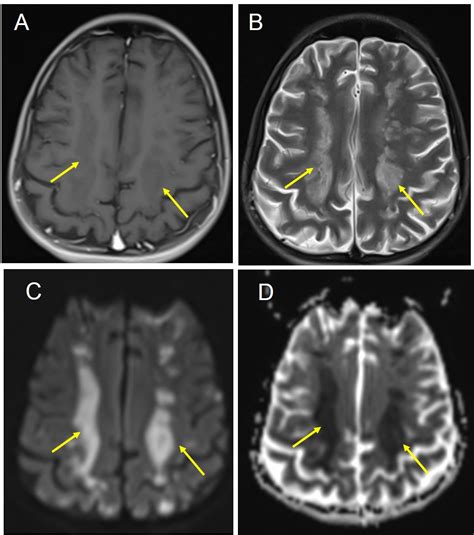

A Watershed Brain Infarct is a specific and critical type of ischemic stroke that occurs in the border zone areas of the brain. Unlike typical strokes that are caused by a blockage in a major artery, these infarctions happen in the "watershed" regions—the most distal areas of blood supply where the territories of two major cerebral arteries meet. Because these areas are the farthest from the heart and rely on the delicate balance of pressure from multiple sources, they are exceptionally vulnerable to drops in systemic blood pressure and reduced blood flow.

• Cortical Watershed Infarct: Located at the borders between the anterior, middle, and posterior cerebral artery territories on the surface of the brain.

• Internal Watershed Infarct: Located in the white matter deep within the brain, often at the border between the deep and superficial arterial systems.

The symptoms of a Watershed Brain Infarct often manifest based on the location of the injury. Patients might experience "man-in-the-barrel" syndrome, where the shoulders and upper arms are weaker than the hands and legs. Other signs include cognitive impairment, language difficulties, or visual field deficits.

MRI (Diffusion-Weighted) The gold standard for visualizing acute ischemic changes.